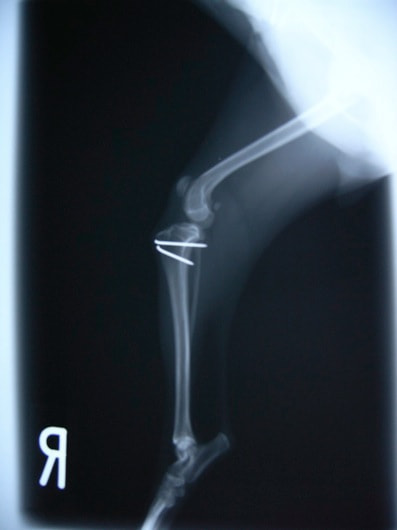

■ 症例20 ポメラニアン 8ヶ月 1.8kg

左右膝蓋骨脱臼 グレードⅢ

2ヶ月前から間欠的跛行が認められ、両膝の膝蓋骨脱臼整復術を行った。

手技は縫工筋及び内側広筋の解放、脛骨粗面の外側転位、滑車ブロック形造溝術、内外側関節包の縫縮を選択し実施した。

右側の膝蓋骨脱臼は上記手技で整復されたものの、左側はそれのみでは膝蓋骨が浮く様子が認められた。その為、PDS縫合糸にて膝蓋靱帯を1糸のみ縫合し、靱帯の縫縮を行った。

膝蓋骨脱臼は膝関節における膝蓋骨の内外側の脱臼と定義されるが、時として単純な内外の脱臼ではなく、膝蓋骨が大きく前方に浮き上がるように脱臼する場合がある。特にトイプードルやポメラニアンといった犬種に多く認められる。

内側脱臼に加えて前方への浮き上がりを矯正する為に、従来より脛骨粗面転移により膝蓋靭帯を外方と下方に引っ張り、固定する方法を選択する。膝蓋骨の前方への浮き上がりが軽度の場合は、従来法ではなく関節包の縫縮で対応していた。しかし、一部の症例で膝蓋骨の動きが悪くなり伸展機構が円滑に機能せずロボット様歩行になるケースがあった。

その為、膝蓋靭帯自体を縫縮する方法を採用した。この方法により、膝関節の伸展機構を妨げず膝蓋骨の軽度の浮きを矯正することが可能となった。

本症例の経過は良好である